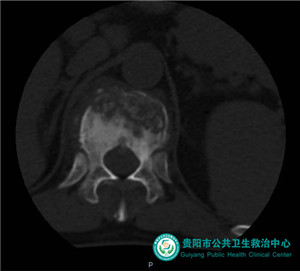

術(shù)前椎體前緣陳舊性缺損、壓縮